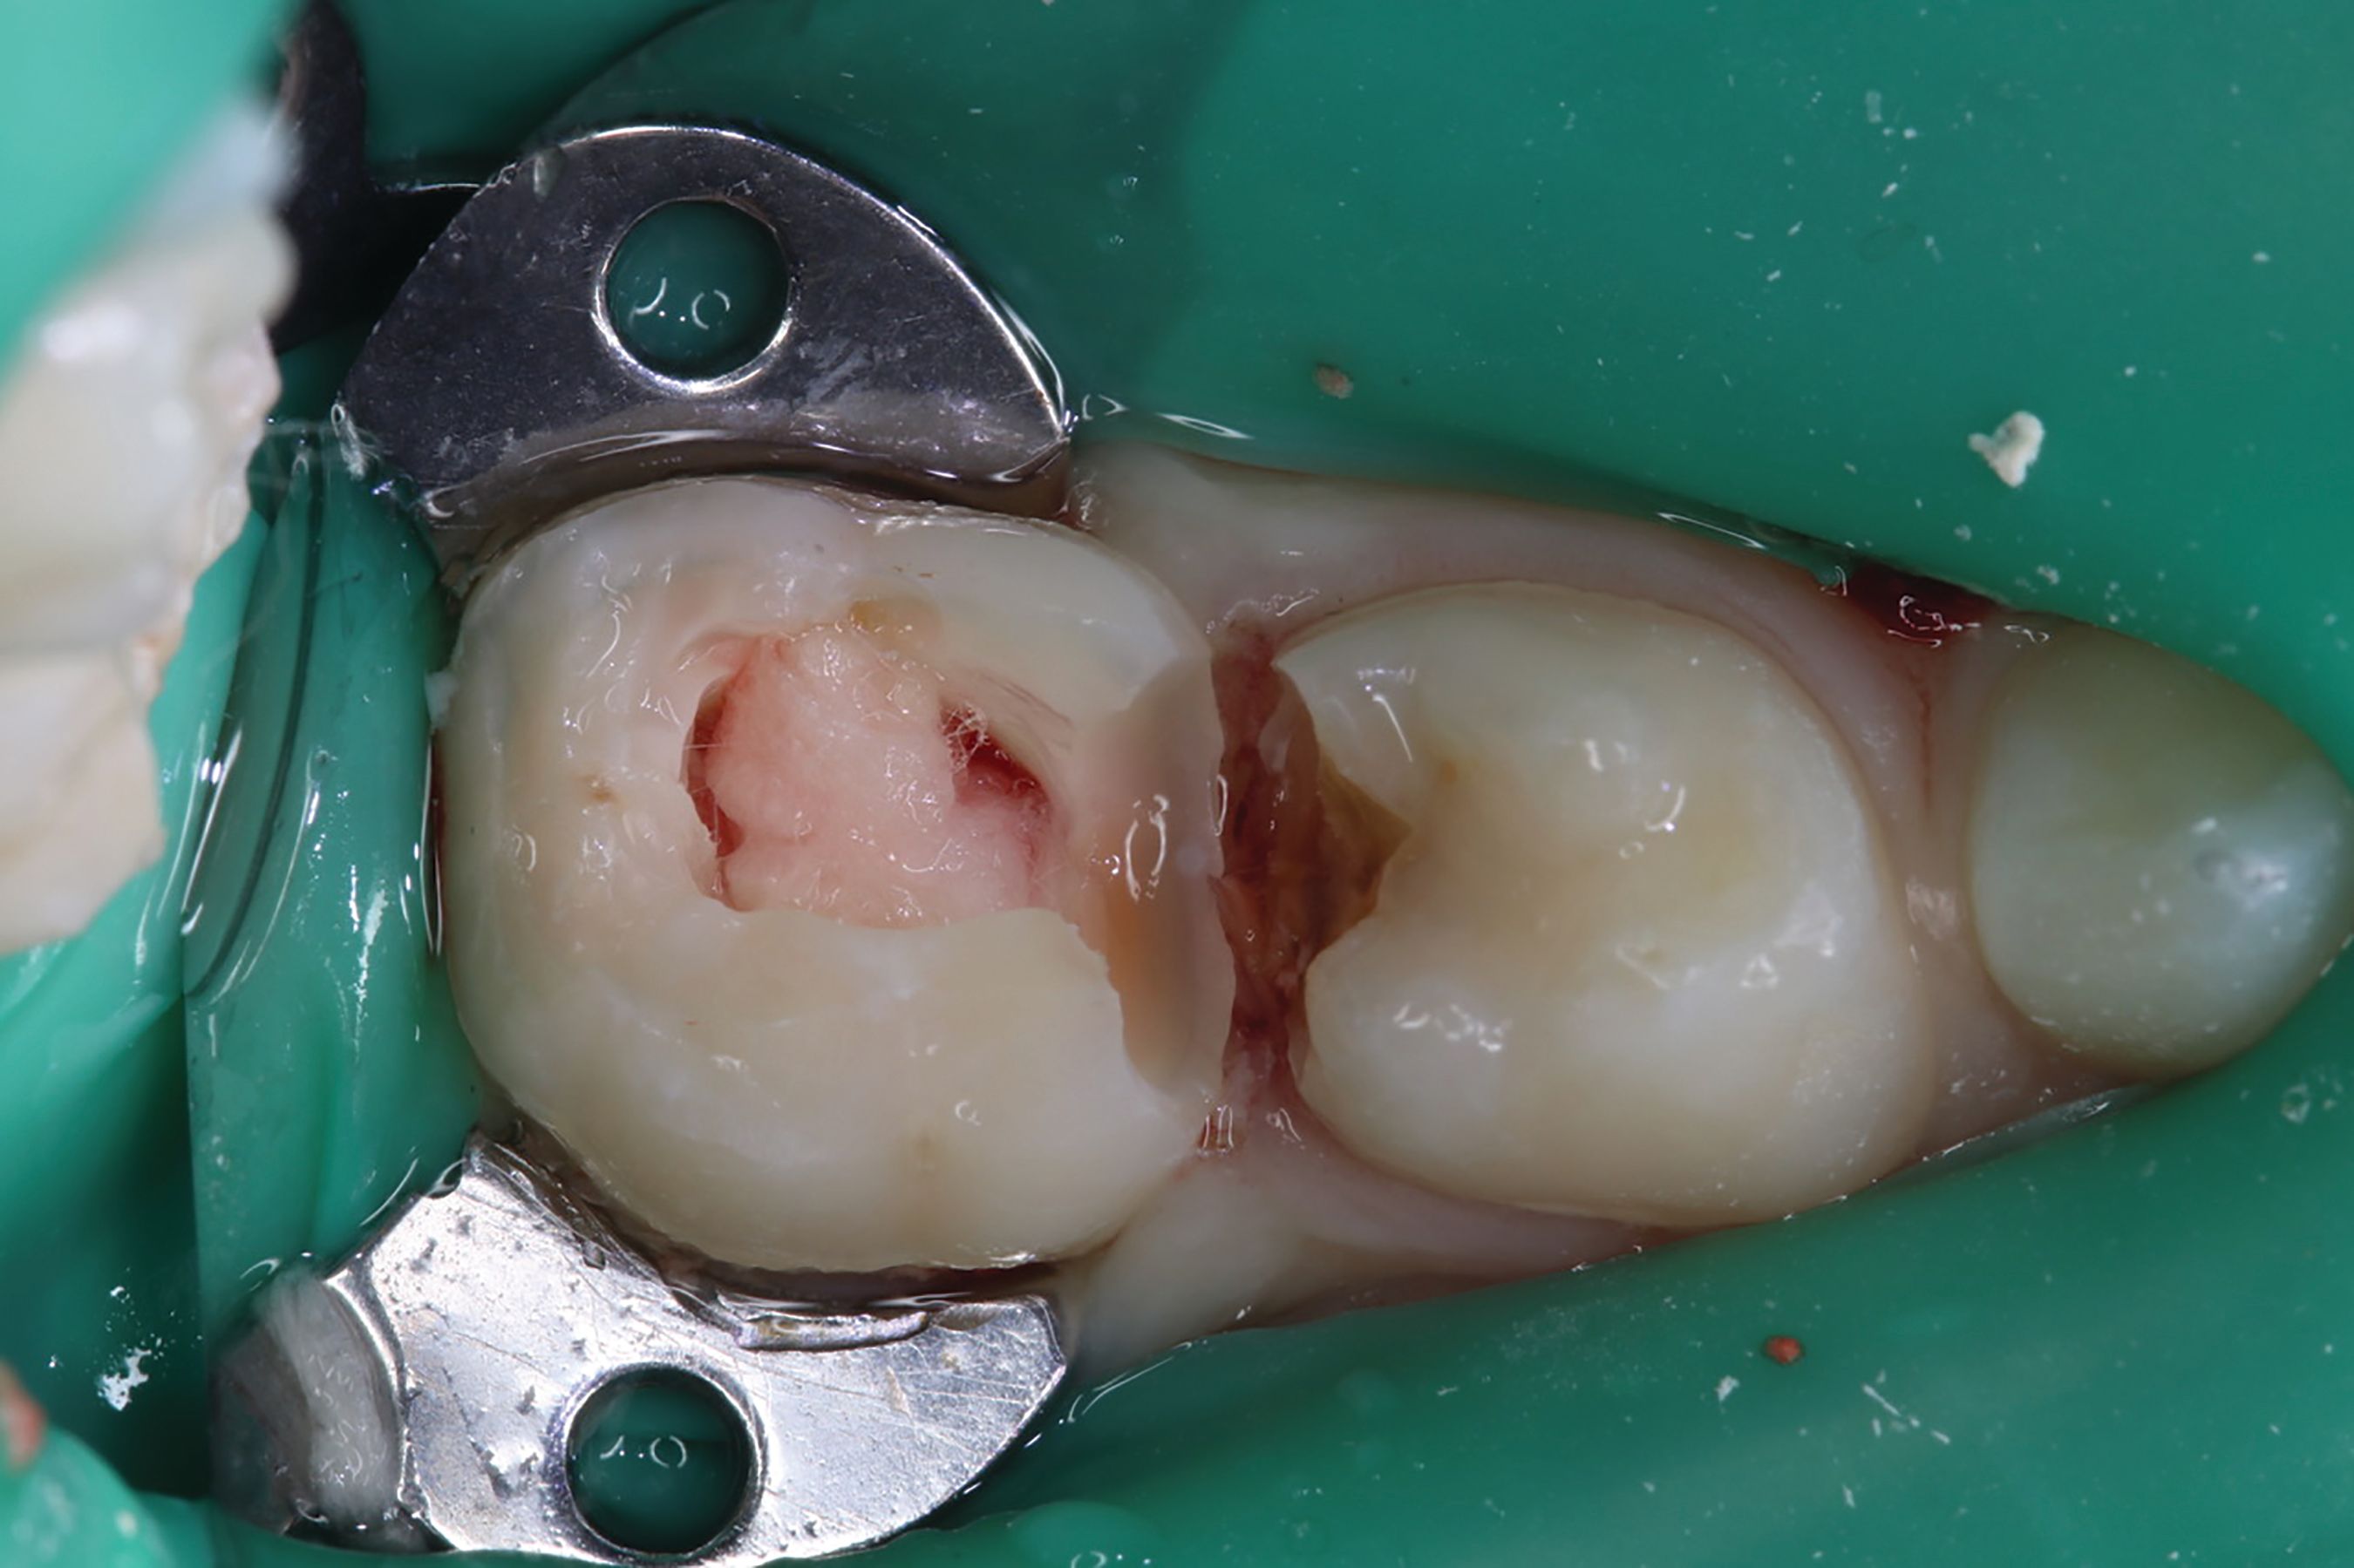

Pre-operative view shown in Figure 1. Primary second molar requiring pulpotomy procedure.

Fig. 1.

[ Figs. 1-9 ] Pre-operative view-primary second molar requiring pulpotomy procedure (Fig. 1). Amputation of coronal pulp chamber to level of radicular pulp stumps with NSK Dental’s slow speed large round bur #8, removing coronal pulp tissue with gentle upward motion (Fig. 2). Hemostasis achieved with saline-soaked sterile cotton pellet (Figs. 3 & 4). Hemostasis achieved (Fig. 5). Extrusion of TheraCal PT into pulp chamber, being sure to reach base of coronal pulp chamber with material and without voids or bubbles and light cure (Figs. 6 & 7). Cured TheraCal PT (Fig. 8). Full-coverage stainless-steel crown (Fig. 9).